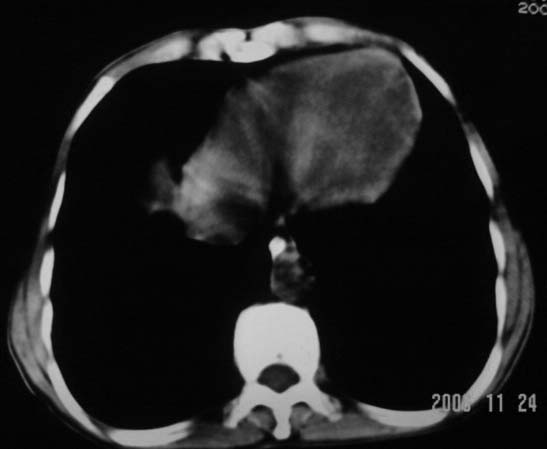

仰卧位见:肝前间隙及肝脾间隙内可见新月形气体密度影,边缘清楚,侧卧位见气体随体位改变而移动,ct值约-929hu。膈下、肝下间隙及部分肠间隙可见液性密度影。考虑:1、上腹部空腔脏器穿孔,以胃穿孔可能性大。2、少量腹水。

仰卧位见:肝前间隙及肝脾间隙内可见新月形气体密度影,边缘清楚,侧卧位见气体随体位改变而移动,ct值约-929hu。膈下、肝下间隙及部分肠间隙可见液性密度影。考虑:1、上腹部空腔脏器穿孔,结合临床,首先考虑胃穿孔可能性大。2、少量腹水

补充--肝门及肝肾间隙以见积气显示。

支持消化道空腔脏器穿孔(腹腔内大量游离气体影,小网膜囊内亦见气体影),少量腹水。